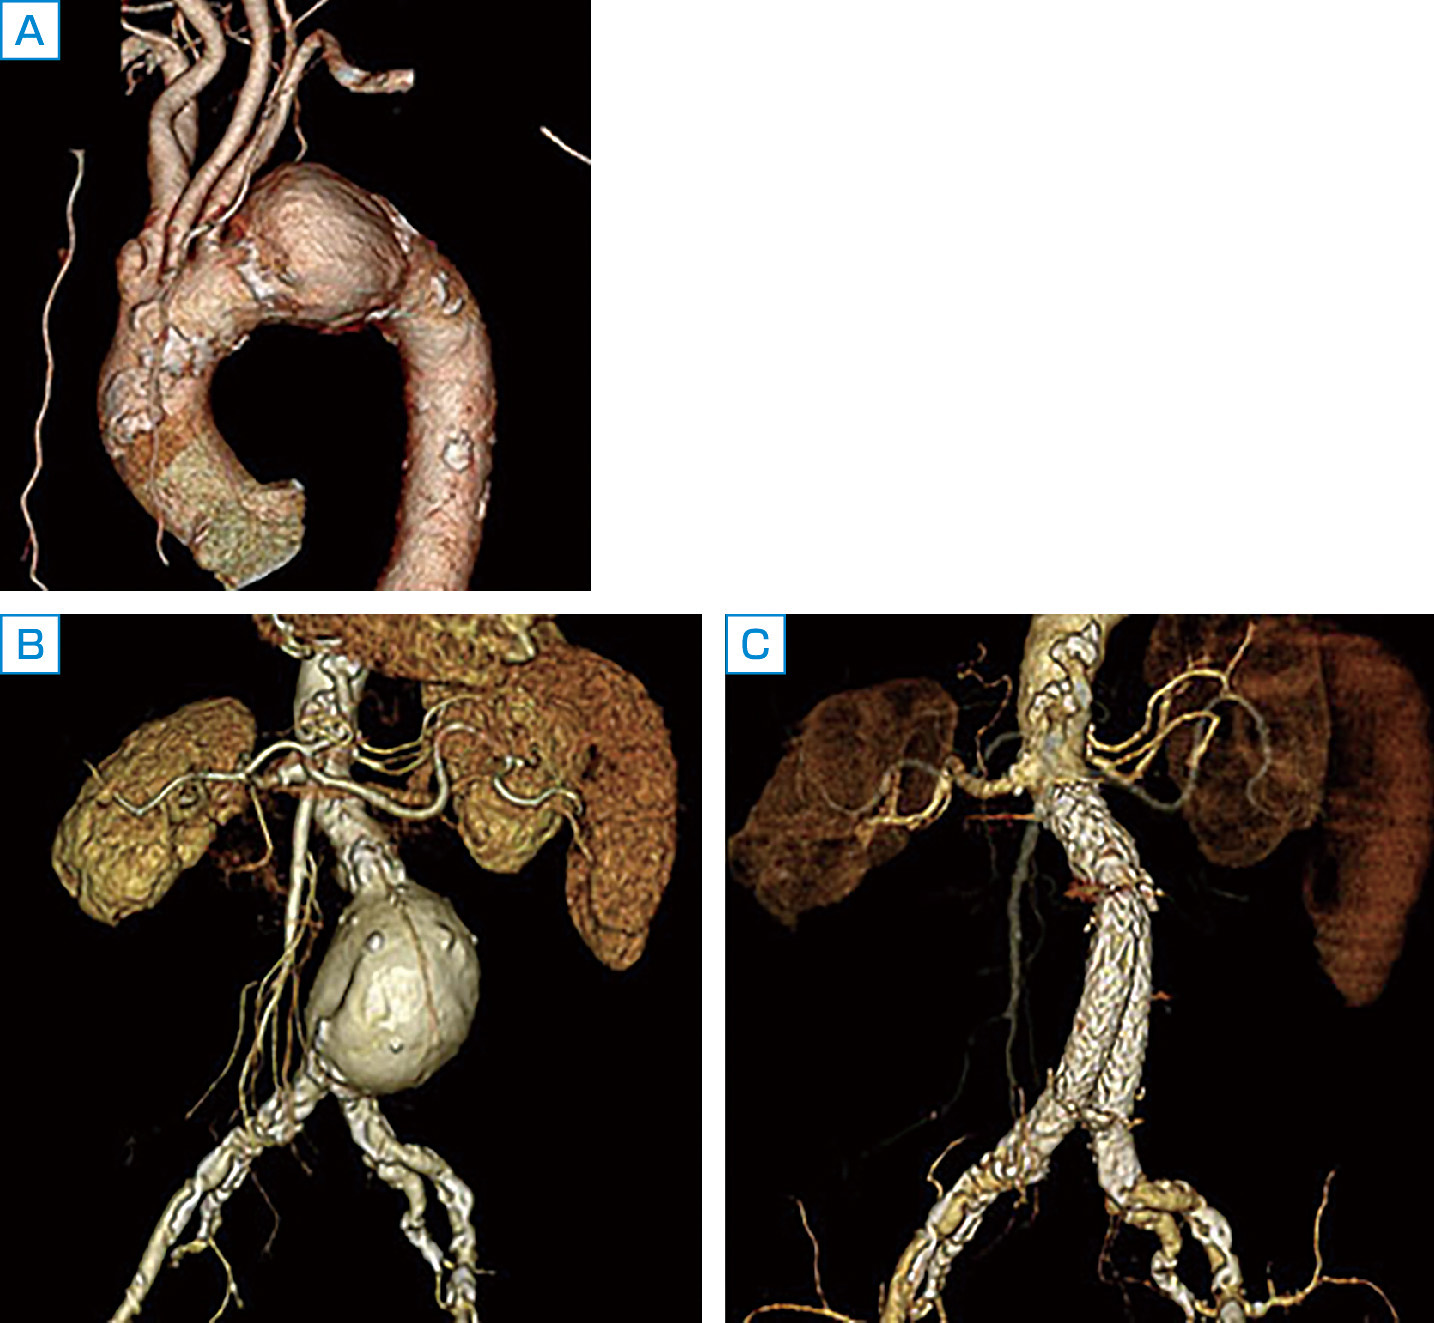

大動脈壁が脆弱化して局所的に全周性または一部が拡張した状態を大動脈瘤とよぶ.一般に,大動脈の外径の直径が正常部位の1.5倍 (目安として胸部大動脈系45 mm,腹部大動脈30 mm) をこえた状態を大動脈瘤と定義する.大部分は無症状のままに経過し,健診や医療機関受診の際の視診や触診,胸部X線写真正面像における縦隔拡大や側面像における拡大,腹部触診や腹部超音波 (図2) やCT (図3),MRI (図4) で発見され診断される.瘤の形状によって,紡錘状あるいは囊状,また壁構造の違いによって,瘤が内膜・中膜・外膜の3層すべてを有する真性動脈瘤と,中膜平滑筋層の連続性が失われ外膜や結合組織によって被包されている仮性大動脈瘤に分類される (図5).大動脈壁脆弱化の原因としては,外傷,梅毒,Marfan症候群などもあるが,最も大きな割合を占めるのは高血圧と加齢に伴う動脈硬化性変化であり,高齢男性に多い.大動脈瘤が解離したり破裂したりすると,激烈な胸背部痛や腹痛を訴えたり,血圧低下しショックに陥ったりする.いったんショック状態に陥った症例はもちろんのこと,病院に搬送されたとしても救命できる可能性は50%以下とされる.瘤径拡大スピードが高いほど,瘤形状が全体的でなく部分的であるほど,また当然,血圧が高いほど破裂リスクは高い.

破裂を防ぐには瘤径の増大に注意しながら,厳格な血圧コントロールが必要である.大動脈瘤・大動脈解離診療ガイドライン (2011年改訂版) で示された胸部および腹部大動脈瘤の慢性期診療指針によると,胸部では瘤の部分の直径60 mm以上,腹部では瘤の直径50 mm以上で破裂リスクが高いと判断され,早期手術の適応となる.なお,直径50 mm未満の胸部大動脈瘤,直径40 mm未満の腹部大動脈瘤では,1~12カ月間隔でCTや超音波検査を行って,年間5 mm以上の拡大を認めるときは手術適応になる.